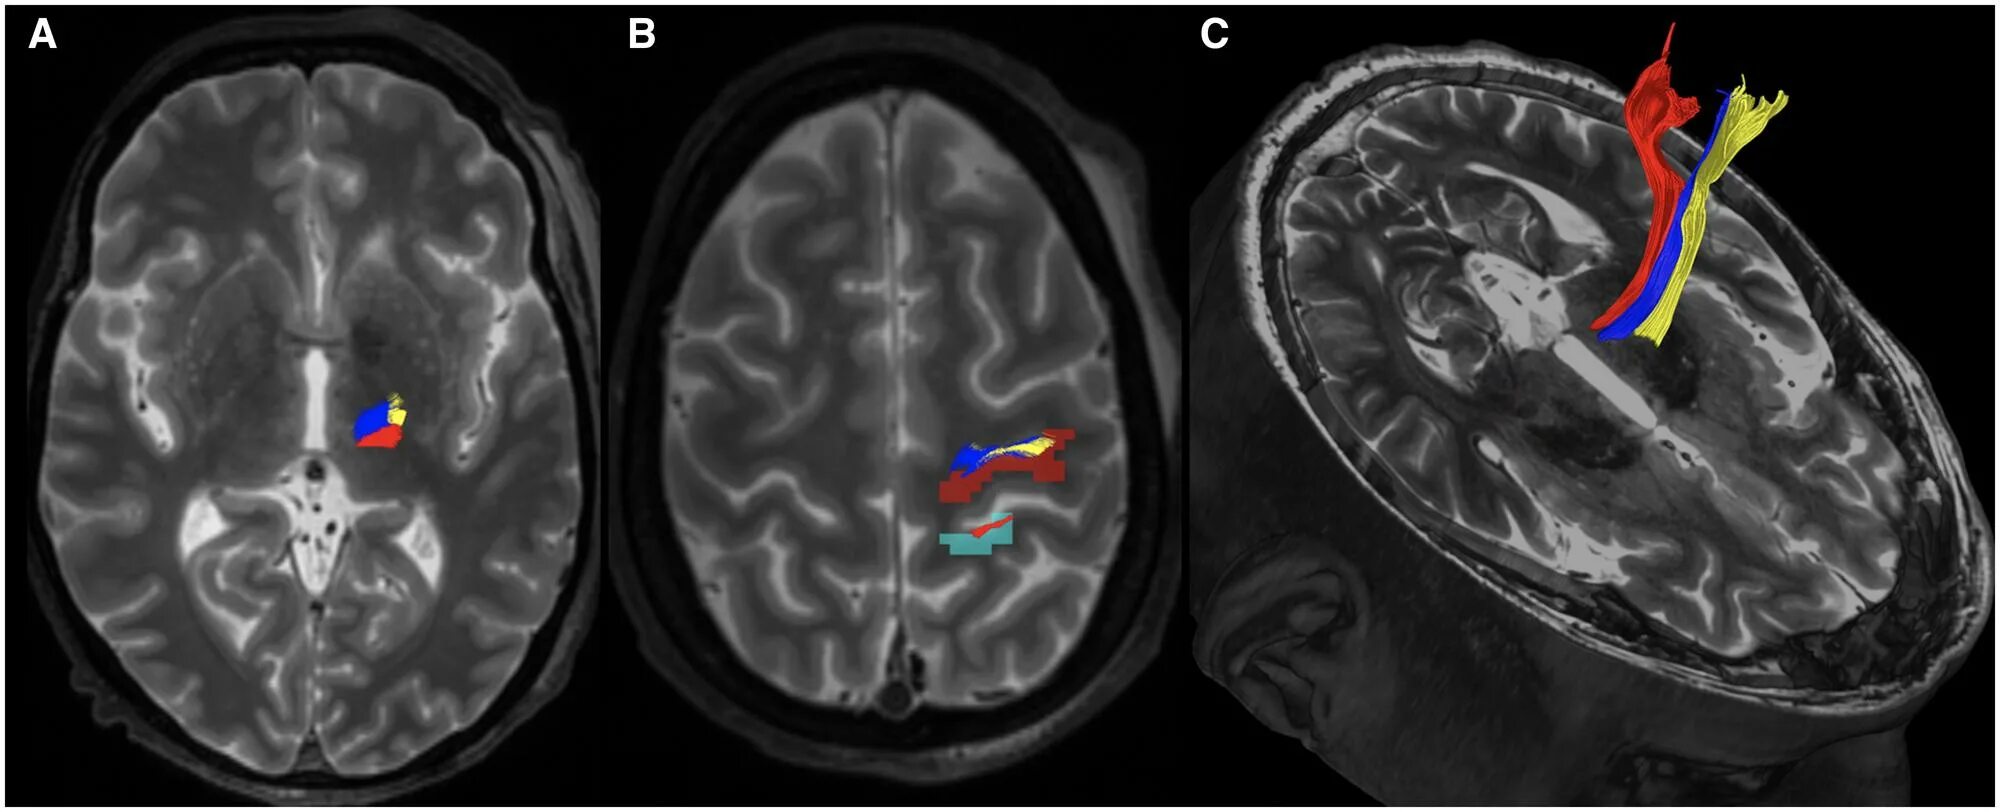

Мрт симптомы